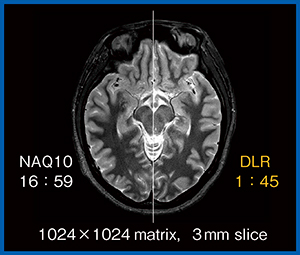

図2は,1024×1024マトリックス,3mmスライス厚の高分解能なPD STIR画像である。低SNRの画像に10回加算(NAQ 10)を行うとSNRが向上するが,撮像時間は約17分である(図2左)。

一方,DLR処理を行うと,1分45秒で10回加算の画像と同等の画質が得られる(図2右)。

図2 高分解能PD STIR画像における10回加算とDLRの比較